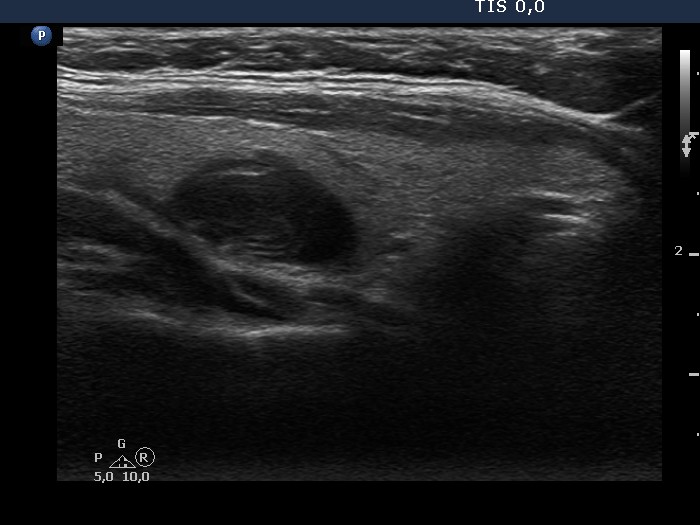

Halo sign and vascular pattern of nodules - case conp 068

Follow-up investigation seven years later (ultrasonographic picture 5)

Middle part of the right lobe, longitudinal scan.